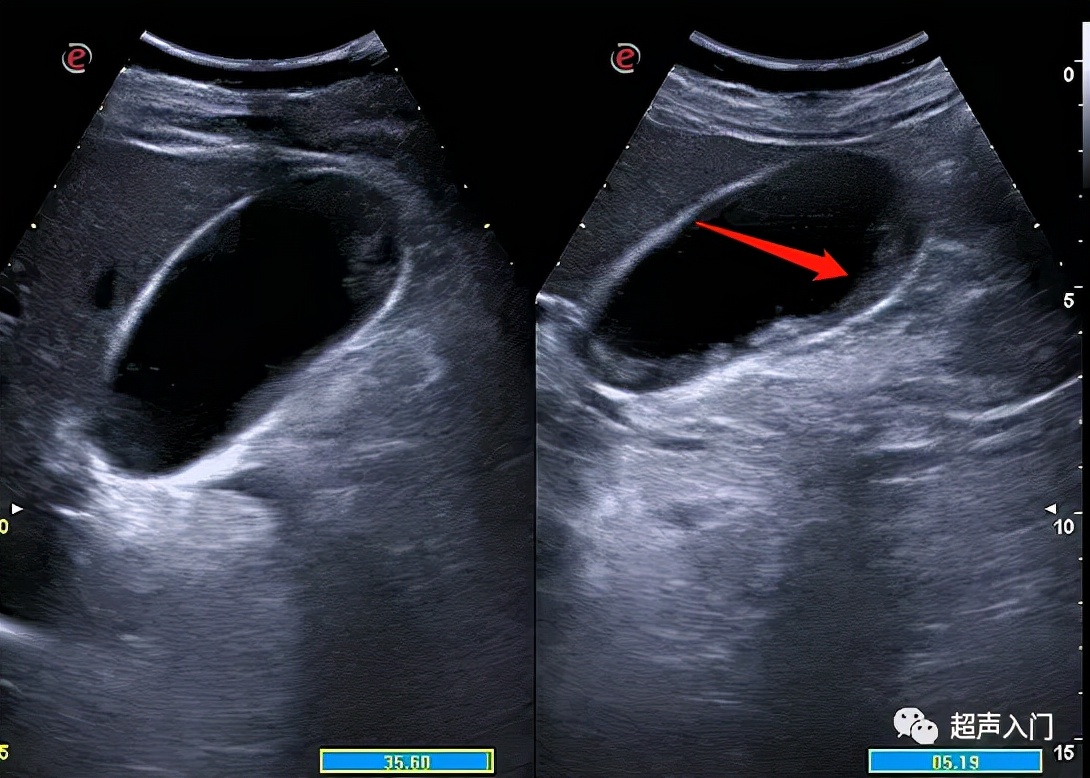

但常规超声往往很难对其进行准确分类,囊内透声好并不代表没有化脓,如上图,囊内透声很好,但患者持续发热,胆囊置管后,抽出脓性胆汁。

3、胆囊切面无回声区内出现稀疏或密集的分布不均的细小或粗大回声斑点,呈云雾状,为胆囊积脓的表现。